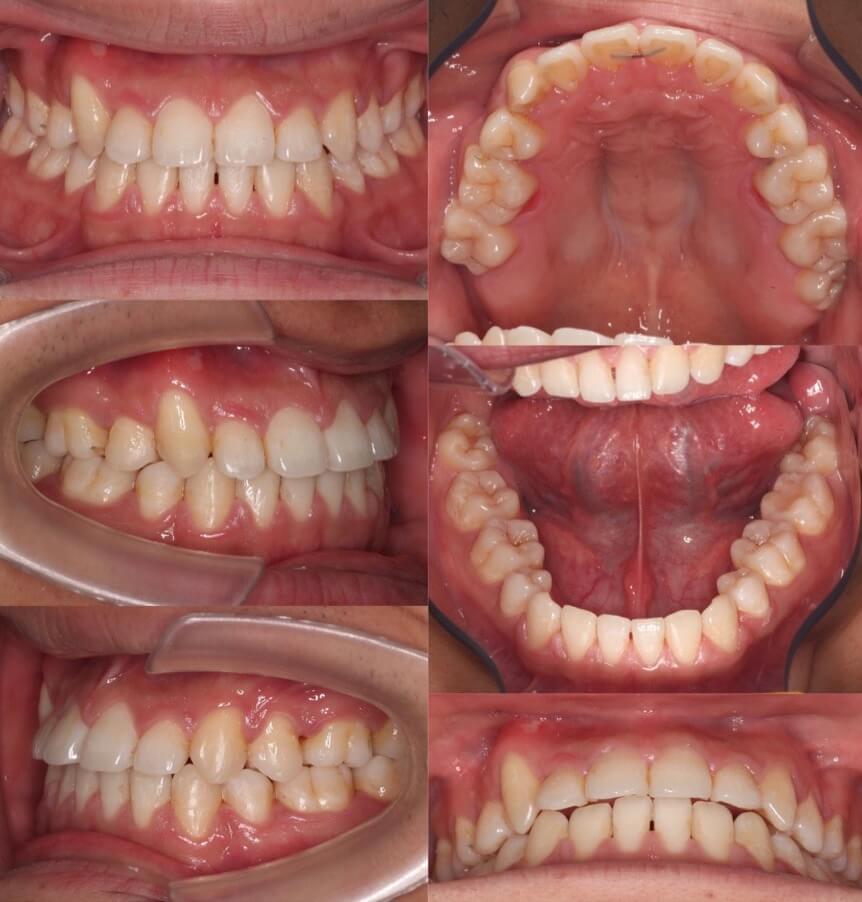

大学生女性・唇側矯正装置・小臼歯4本抜歯

<顔のビフォーアフター>

<症例概要>

主訴:受け口・前歯のガタガタ

年齢・性別:大学生女性

住まい:千葉県八千代市

症状:反対咬合・重度叢生・開咬

治療方針:上下小臼歯抜歯・空隙閉鎖

治療装置:唇側矯正装置

固定装置:上バイヘリックス装置・III級顎間ゴム

抜歯:上第二小臼歯・下第一小臼歯・下親知らず(計6本)

治療期間:2年2か月

リテーナー:上下フィックスタイプ+クリアタイプ

治療費用:968,000(税込)

代表的副作用:痛み・治療後の後戻り・歯根吸収・歯髄壊死・歯肉退縮

▶︎その他の副作用

歯が並ぶスペース不足が大きく、前歯の不揃いが強いケースです。また、上下の前歯は開咬状態になっており咀嚼障害もあります。上下小臼歯抜歯を行いできたスペースをうまく利用して前歯を並べ、III級顎間ゴムを使用し下の歯列全体を親知らずを抜歯した後方へ起こしました。非常に難しい治療方針でしたが、ご本人がゴムの使用を頑張ってくれたので予定より早く治療期間も終わり、審美的にも機能的にも良い歯並びになりました。